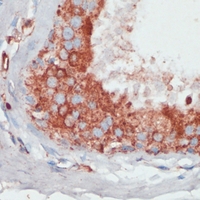

Immunohistochemical analysis of PGK2 staining in human breast cancer formalin fixed paraffin embedded tissue section. The section was pre-treated using heat mediated antigen retrieval with sodium citrate buffer (pH 6.0). The section was then incubated with the antibody at room temperature and detected using an HRP conjugated compact polymer system. DAB was used as the chromogen. The section was then counterstained with haematoxylin and mounted with DPX. -